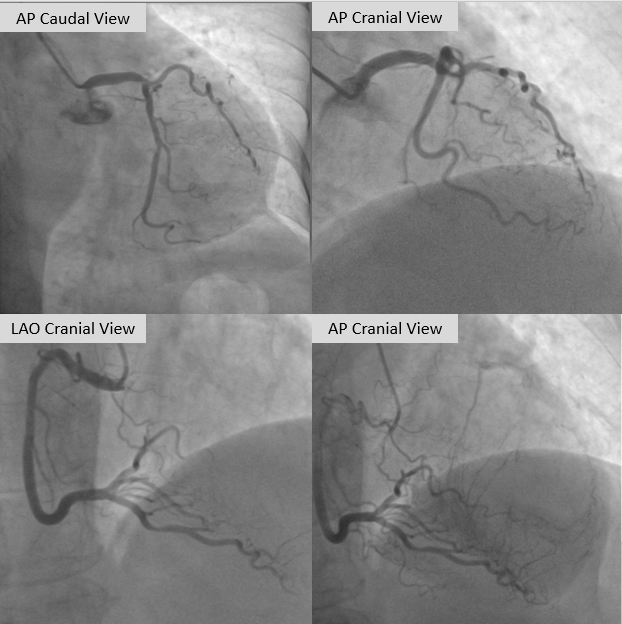

Coronary angiography demonstrated a normal left main artery. The left anterior descending (LAD) artery was totally occluded from the ostium, with distal segments receiving collateral supply from the contralateral circulation, Rentrop grade III. The left circumflex (LCX) artery showed a moderate lesion in its distal portion, while the right coronary artery (RCA), a dominant vessel, has moderate lesion from the proximal to mid segments. PCI for the LAD CTO was stagged within the next two weeks.

An ultra low contrast PCI of the LAD was performed using dual puncture with EBU 3.5/7F and JR 3.5/6F catheters via radial and femoral access. Saline was used for engagement, with contrast restricted to microcatheter injections of 1 cc each as a sparing strategy. Antegrade proximal cap puncture with Finecross and Fielder XTA tracked subintimally, and a parallel wire technique with Gaia Next 2 successfully crossed the lesion, confirmed by retrograde injection. Lesion preparation was achieved with a semicompliant balloon (2.5 ¡¿ 15 mm) from mid to proximal LAD and a cutting balloon (2.75 ¡¿ 18 mm) from mid to ostium LAD. IVUS pullback revealed a long diffuse lesion with proximal and ostial calcification, showing calcium cracks after preparation. MLA at the ostium LAD was 2.5 mm©÷, distal reference diameter 2.8 mm, and LM diameter 4.5 mm. Stent deployment was guided by multiple wires as anatomical landmarks without contrast. A DES (3.5 ¡¿ 28 mm) was implanted from distal LM crossover to proximal LAD, followed by POT with a 4.0 ¡¿ 9 mm NC balloon. A second DES (2.75 ¡¿ 28 mm) was placed in proximal to mid LAD overlapping the first, with post-dilation using a 3.0 ¡¿ 15 mm NC balloon. IVUS confirmed well-expanded, well-apposed stents without edge dissection. Final MSA was 12 mm©÷ in LM, 10.8 mm©÷ in ostium LAD, and 6.3 mm©÷ in mid LAD. Final angiography with diluted contrast demonstrated TIMI 3 flow, with total contrast use limited to 12 cc.